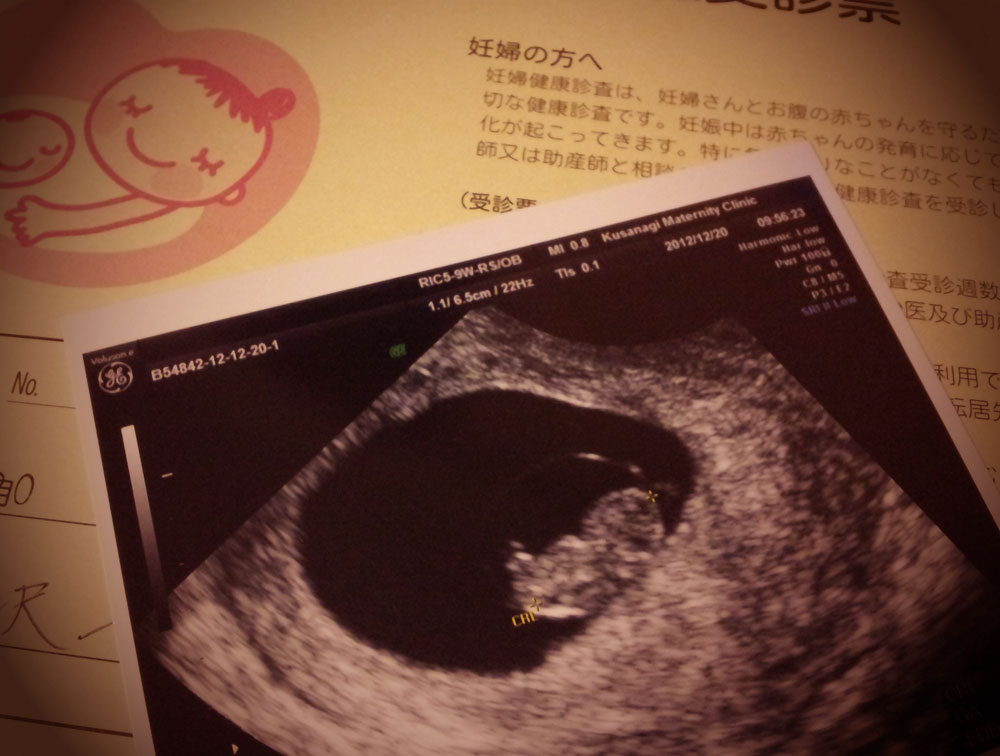

医師監修 妊娠9週のエコー写真 手足が動かしはじめることも マイナビ子育て

妊娠9週目 9w0d 6d のエコー写真とエピソード 妊娠3ヶ月 Cozre コズレ 子育てマガジン

医師監修 妊娠9週のエコー写真を多数掲載 みんなのエピソードつき 年9月17日 ウーマンエキサイト 1 3